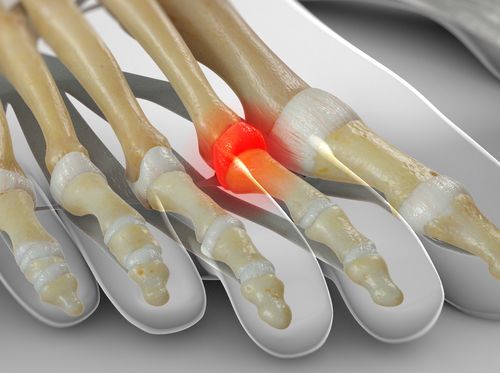

Metatarsalgia: es el dolor en la parte delantera del pie, donde están los metatarsos (justo antes de la base de tus deditos). Al caminar casi de puntillas o cargar más peso adelante (porque el talón no baja bien), esa zona del antepié soporta más presión de la normal y puede doler, sobre todo al estar mucho tiempo de pie o con calzado inadecuado.

Neuroma de Morton: suena complicado, pero básicamente es la irritación de un nervio entre los dedos del pie (usualmente entre el tercero y cuarto dedo) que causa dolor o calambres en el antepié. Si hay demasiada presión en la parte delantera del pie (otra vez, por culpa de unos gemelos rígidos que no dejan apoyar bien el talón), los nervios entre los dedos pueden quedar aplastados o irritados. Sientes como una especie de corriente, ardor o piedrita en el zapato al pisar.